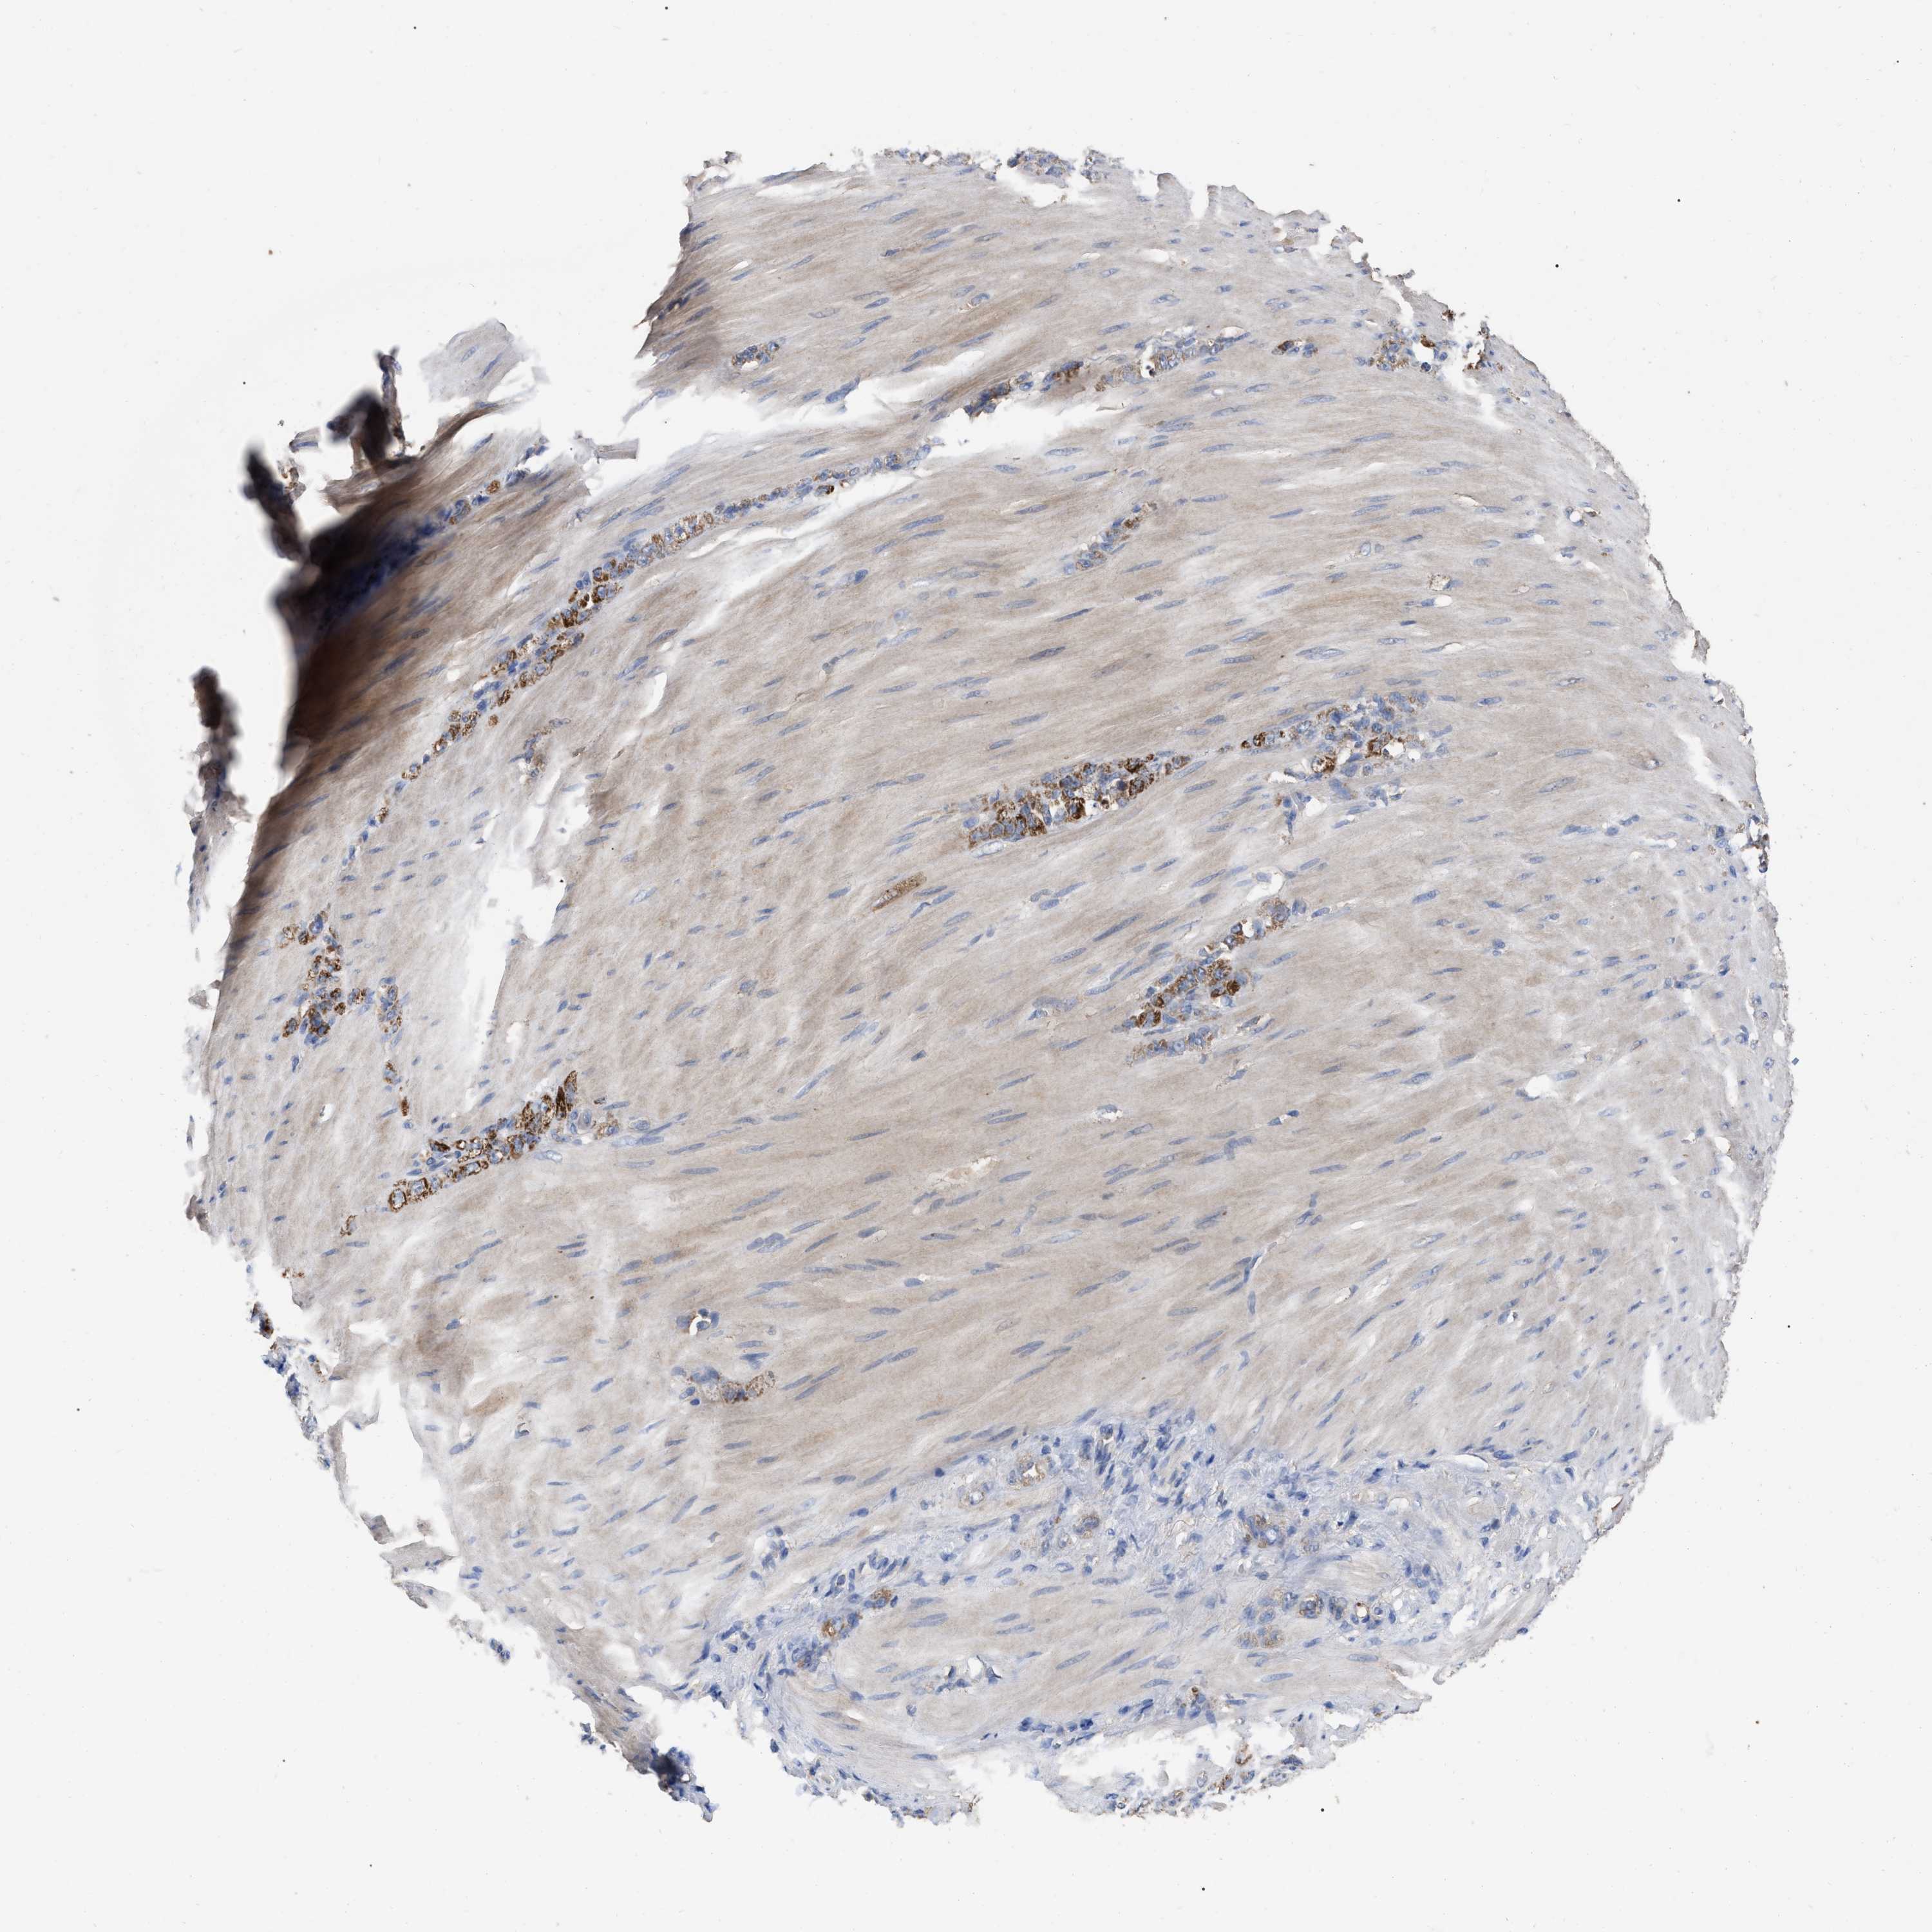

STOMACH CANCER - Protein expressioni

A mouse-over function shows sample information and annotation data. Click on an image to view it in a full screen mode. Samples can be filtered based on level of antibody staining by selecting one or several of the following categories: high, medium, low and not detected. The assay and annotation is described here.

Note that samples used for immunohistochemistry by the Human Protein Atlas do not correspond to samples in the TCGA dataset.

Antibody stainingi

Antibody staining in the annotated cell types in the current human tissue is reported as not detected, low, medium, or high, based on conventional immunohistochemistry profiling in selected tissues. This score is based on the combination of the staining intensity and fraction of stained cells.

Each image is clickable and will lead to virtual microscopy that enables deeper exploration of all samples and also displays staining intensity scores, fraction scores and subcellular localization as well as patient and tissue information for each sample.

Antibody HPA017885

Staining

High

Medium

Low

Not detected

Intensity

Strong

Moderate

Weak

Negative

Quantity

>75%

75%-25%

<25%

None

Location

Nuclear

Cytoplasmic/membranous

Cytoplasmic/membranous,nuclear

Adenocarcinoma, NOS